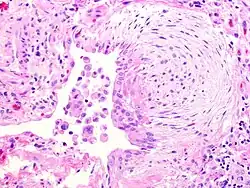

Vesicular mole | Micrograph of vesicular mole showing oedematous chorionic villus with circumferential proliferation of trophoblasts. | Category: Histopathology of chorionic villi | chorionic villi |

![]() |